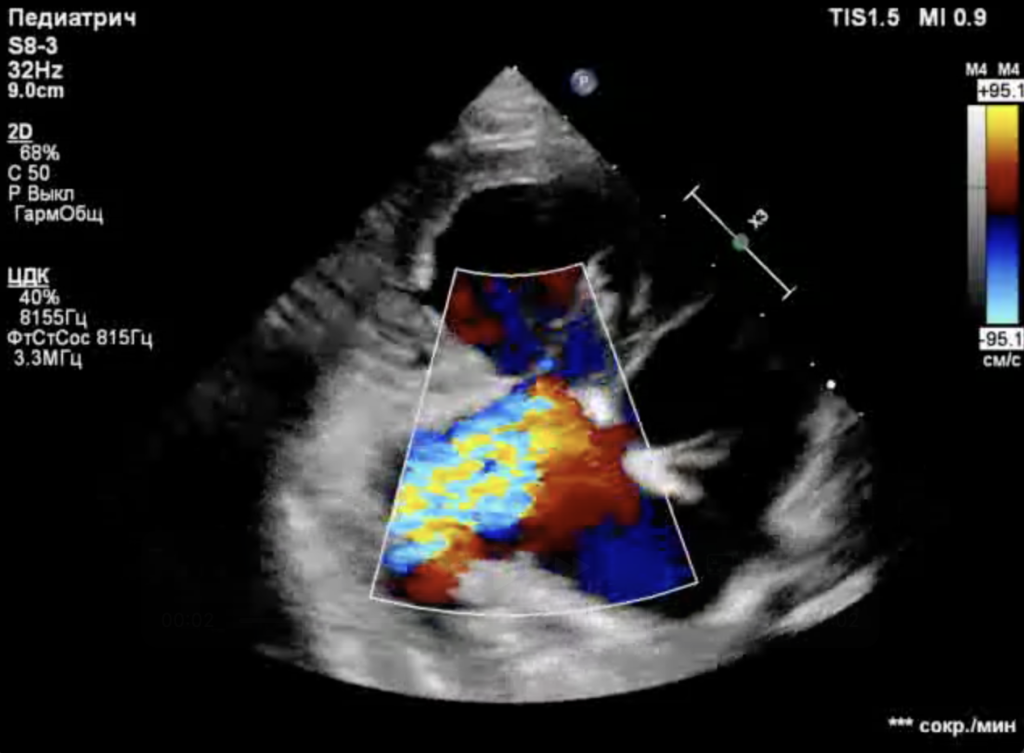

Спустя 8 дней после проведения операции было выполнено контрольное эхокардиографическое исследование, результаты которого выявили следующие изменения (фото 6-8):- Конечный диастолический размер (КДР) правого желудочка снизился с 34 до 22 мм.

- Площадь регургитационного отверстия уменьшилась с 2,7 до 0,7 см2.

- Степень регургитации - moderat/severe.

- Отсутствие застоя в системных венах.

- Систолическая функция ПЖ – в пределах нормы.